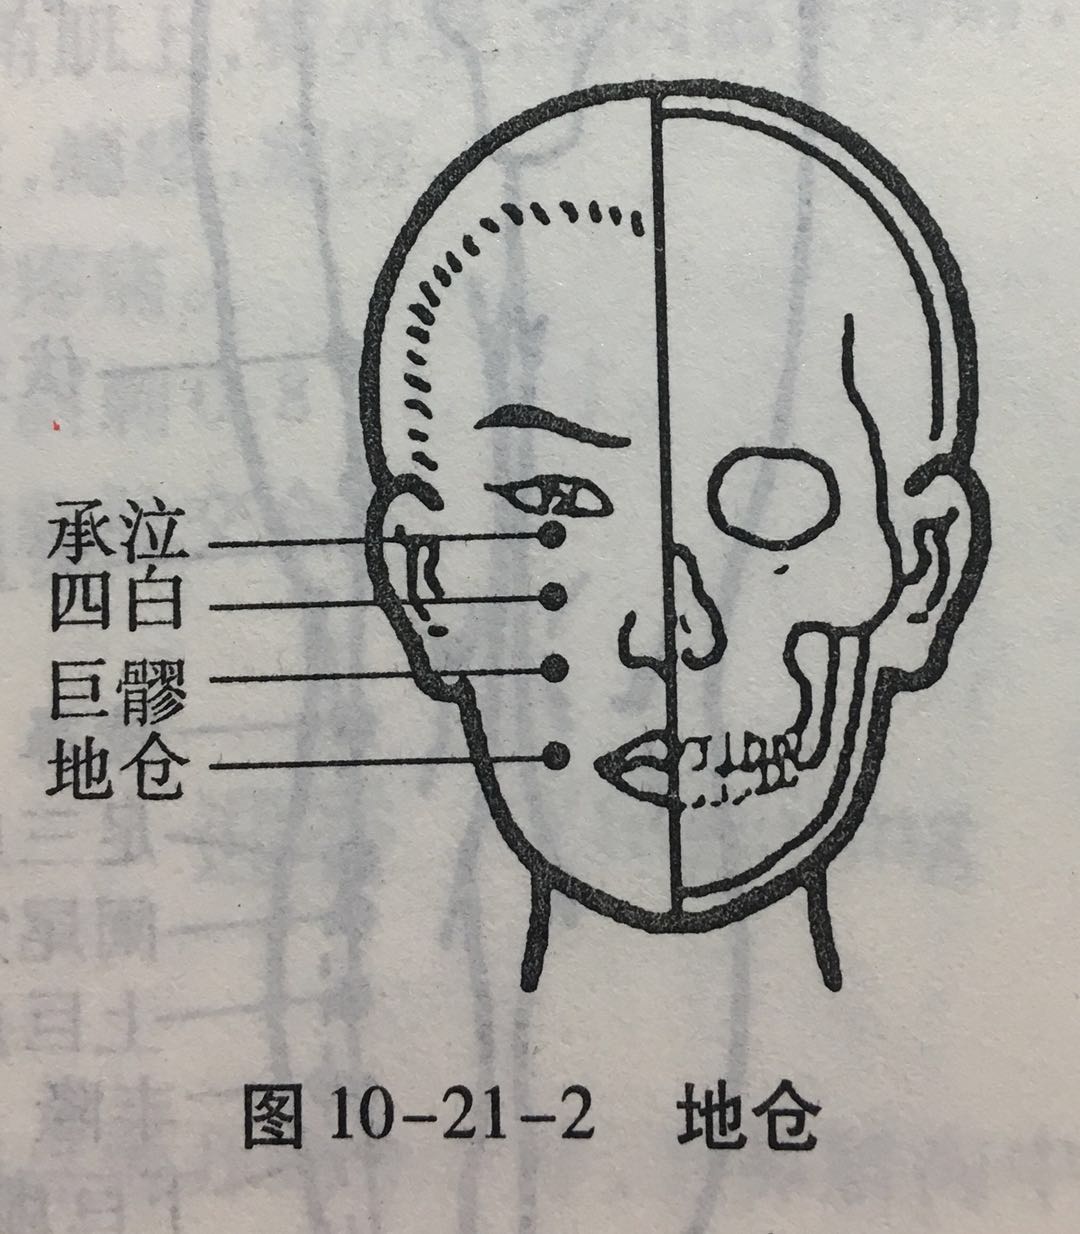

地仓

【定位】 在面部,口角旁约 0.4 寸,上直对瞳孔(图 10-21-2)。

【主治】 口歪,流涎,口角瞤(rún)动。

【配伍】 配颊车、合谷治口歪、流涎。

【刺灸法】 向颊车方向平刺 0.5 ~ 0.8 寸。

【附注】 手足阳明经、阳跷脉交会穴。